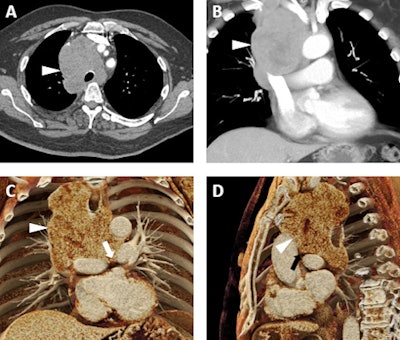

A 92-year-old man with a history of aortic stenosis initially treated with an open surgical procedure to place a bioprosthetic aortic valve and subsequently revised by endovascular replacement of a CoreValve. A-C: Volume-rendered images demonstrate the CoreValve (white arrowheads) inside the bioprosthetic valve (white arrows). The patient also has a patent saphenous vein-to-left anterior descending artery bypass graft (thin white arrow in C). D-F: Cinematic-rendered images also demonstrate the CoreValve (black arrowhead in D and white arrowheads in E and F) within the older bioprosthetic valve (black arrow in D and white arrow in E). The patient's patent saphenous vein graft is also apparent in D (thin black arrow). The photorealistic quality of the volume-rendered images may find eventual application in aiding vascular surgeons and other interventionalists by allowing the diagnosis of subtle thromboses or other valve-related pathologies that are not as apparent with less detailed visualizations.